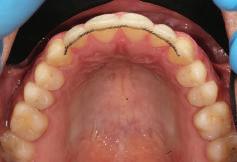

11Dental Tribune Bulgarian Edition / октомври 2022 г. Преди лечението Фиг. 1 Фиг. 2 Фиг. 3 Фиг. 4 Фиг. 5 Фиг. 6 Фиг. 7 Фиг. 9 Фиг. 10 Фиг. 11 Фиг. 8 Фиг. 12 Фиг. 13

12 Dental Tribune Bulgarian Edition / октомври 2022 г. По време на лечението Фиг. 14 Фиг. 16 Фиг. 20 Фиг. 23 Фиг. 21 Фиг. 24 Фиг. 26 Фиг. 28 Фиг. 31 Фиг. 34 Фиг. 29 Фиг. 32 Фиг. 35 Фиг. 30 Фиг. 33 Фиг. 36 Фиг. 27 Фиг. 22 Фиг. 25 Фиг. 17 Фиг. 18 Фиг. 19 Фиг. 15

13Dental Tribune Bulgarian Edition / октомври 2022 г. След лечението За авторите: Д-р Калин Маринов е специалист в областта на имплантологията, протетиката и естетичната хирургия. Завършил е дентална медици на в София през 2012 г. През 2014 г. основава Sky Dental Clinic. Бил е на обмен ни начала в катедра „Протетика“ на Университета по дентална медицина във Фрайбург, Германия. Живял е и е практикувал в Мелбърн, Австралия, и е посеща вал курсове и лекции в Италия, Швейцария, Германия с насоченост в естетич ната хирургия и имплантология, както и тоталната рехабилитация на устна та кухина чрез импланти. Зт. Стефан Петров основава собствена лаборатория през 2006 г. Официален демонстратор на GC за България, като от 2015 г. е KOL за Източна Европа. Инструктор е на Straumann за България. Лаборатория та му има сертификат за пилотна лаборатория на Micerium – Италия. Носител е на множество награди в денталния конкурс „Усмивка на годината”. Носител е на награда CERAMISTS MASTER CUP с д-р Софиен Риахи в престижния международен конгрес CERAMISTS – NO LIMITS 2015 г. Изнася лекции и провежда курсове в редица европейски страни. Фиг. 37 Фиг. 40 Фиг. 43 Фиг. 45 Фиг. 47 Фиг. 50 Фиг. 48 Фиг. 49 Фиг. 41 Фиг. 44 Фиг. 46 Фиг. 42 Фиг. 38 Фиг. 39